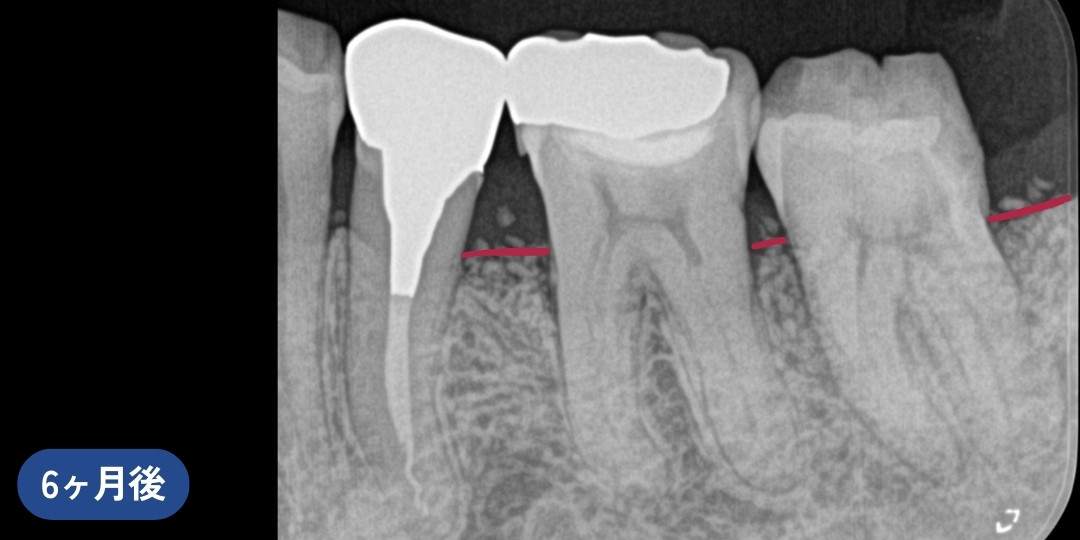

リグロスを用いた歯周組織再生療法後、骨の再生が認められました。※写真内赤線箇所

再生療法6ヶ月後、赤線箇所の骨の回復が確認されました。

再生療法後、赤線箇所の骨の回復が確認されました。

治療後は、歯ぐきの状態が安定し、約半年後のレントゲンで骨の回復傾向が確認されました。